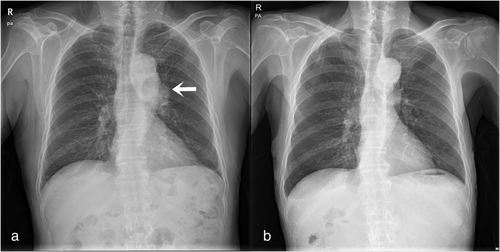

胸部X线检查显示,左肺门有轮廓突出的病变(图1a)。胸部CT显示左上叶恶性肿瘤,左肺门和纵隔淋巴结肿大(图2a、b)。由于外生型病变不清晰可见,支气管镜活检失败。医生对患者进行了视频辅助胸腔镜手术(VATS),切除了主动脉下淋巴结。

图片图1:(a)胸部X线检查显示左肺门轮廓突出的病变;(b)胸部X线检查先前左肺门轮廓突出的病变完全消失

“奇迹”出现了!胸部X线检查没有显示左肺门有轮廓突出的病变(图1b)。胸部CT扫描证实,先前左上叶、纵隔和肺门的SCLC完全缓解(图2c、d)